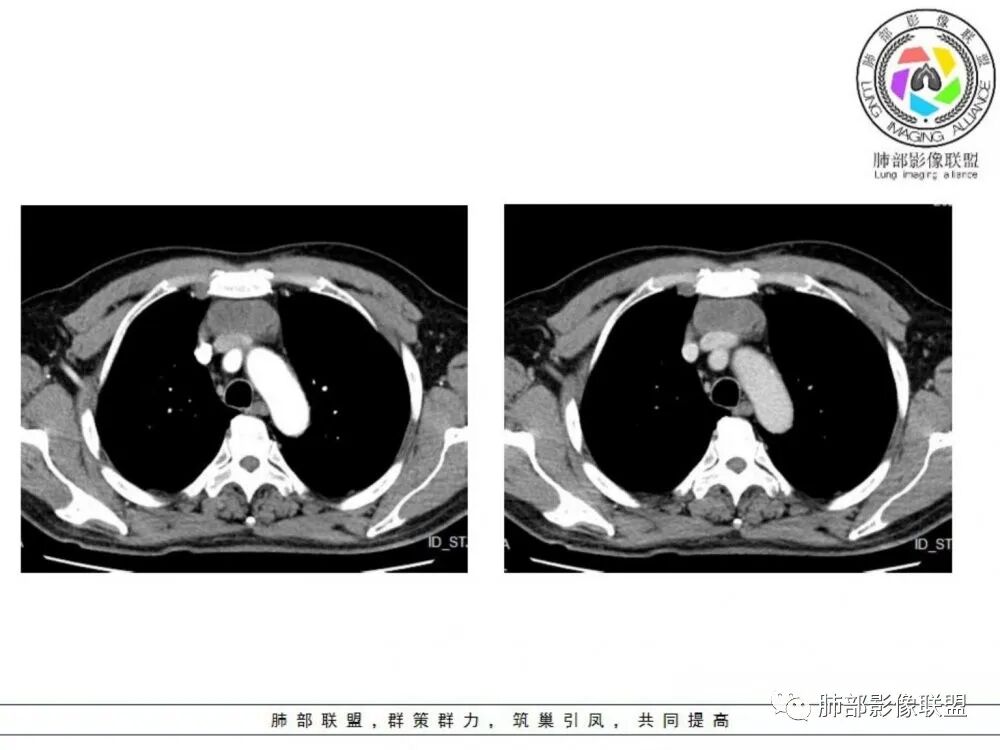

男性患者,65岁,前胸后背疼痛一个月。影像学前上纵隔分叶状的软组织肿块,肿块形态怪异,偏软,位于大血管间隙前,并有向血管后间隙发展的趋势,平扫CT值为40左右,增强扫描中心部未见强化,周围轻度的强化,约为50左右。前上纵隔的疾病谱包抬胸廓内甲状腺肿、胸腺瘤/癌、畸胎瘤、淋巴瘤。少见的心包囊肿或支气管囊肿。根据肿块的形态及强化特点,首先还是排除了胸内甲状腺肿及胸腺来源的肿物,这类的肿物强化比较明显。畸胎瘤成分比较复杂,具有软组织钙化或者脂肪类的组织,这个肿物虽然在平扫的时候好像有斑点状的钙化灶,但是总体成分还是比较单一,所以还是排除畸胎瘤的诊断。所以这样的情况是考虑:淋巴类的肿瘤,注意排除心包的囊肿或支气管来源的囊肿。

老年男性患者,前膈软组织肿块,边缘轮廓不光整,边界似乎尚清晰,内见小点状钙化灶,平扫密度欠均匀,增强后轻度强化表现,边缘有些斑片状的高强化区。综合考虑胸腺瘤或胸腺鳞癌,神经内分泌癌强化弱了一些。患者年龄较大,生殖细胞肿瘤不考虑,淋巴瘤血管包绕不够,可能性不大

老年男性,前胸后背痛一个月,前纵隔不规则肿块,分叶,向纵隔血管间隙进入,且与纵隔血管分界不清,增强边缘轻度强化,中间可见无强化区,似见点状钙化,PET为高代谢,考虑为来源于胸腺,胸腺瘤或胸腺鳞癌可能

老年男性,前纵隔不规则软组织肿块影,密度欠均匀,与大血管分界欠清,上腔静脉局部包绕受侵,增强扫描不均匀轻度强化,PET-CT高代谢。考虑恶性肿瘤性病变,胸腺癌可能。鉴别淋巴瘤。

前纵隔胸腺区分叶状软组织肿块影,轻度不均匀强化,中心可见坏死,边缘不清,病灶与邻近心包见条索影,上腔静脉受侵,上纵隔多发小淋巴结,考虑胸腺鳞癌可能。

中老年男性,前纵隔占位,基本居中,向两侧生长;边缘膨隆分叶,部分边界不清,增强不均匀轻中度强化,坏死区边界不清;周围多发增大淋巴结,考虑恶性。主要在胸腺癌、胸腺瘤、淋巴瘤之间鉴别。病灶偏软,有钻缝样生长,这些征象偏向于淋巴瘤。但此例老年患者,病灶内有点状钙化,缺乏结节堆砌感,倾向胸腺癌诊断。